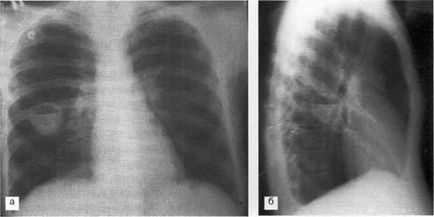

Caracteristica umbră inel închis cu pereți groși și o circulară decolorat în interior, de multe ori în combinație cu întunecare partea inferioară a formațiunii, nivelul separat orizontal de iluminare (fluid la interfața cu aer) da formarea parenchimului pulmonar cavitară în prezența posturilor cavitate cu aerul exterior. Formarea unor astfel de goluri tipice de abcese pulmonare (figura 2), și prezența în interiorul cavității blocări - abcese gangrenoasă (Figura 3) sunt drenate prin arborele bronsic.

Fig. 2. Roentgenograma pacientului K. 38 ani, în proiecțiile laterale (a) și laterale (b). În S6 a plămânului drept, este definită o umbră inelară închisă cu pereți groși - o cavitate umplută cu lichid (2/3 din volumul cavității) cu un nivel orizontal și aer. Abcesul plămânului drept, parțial drenat prin bronhii